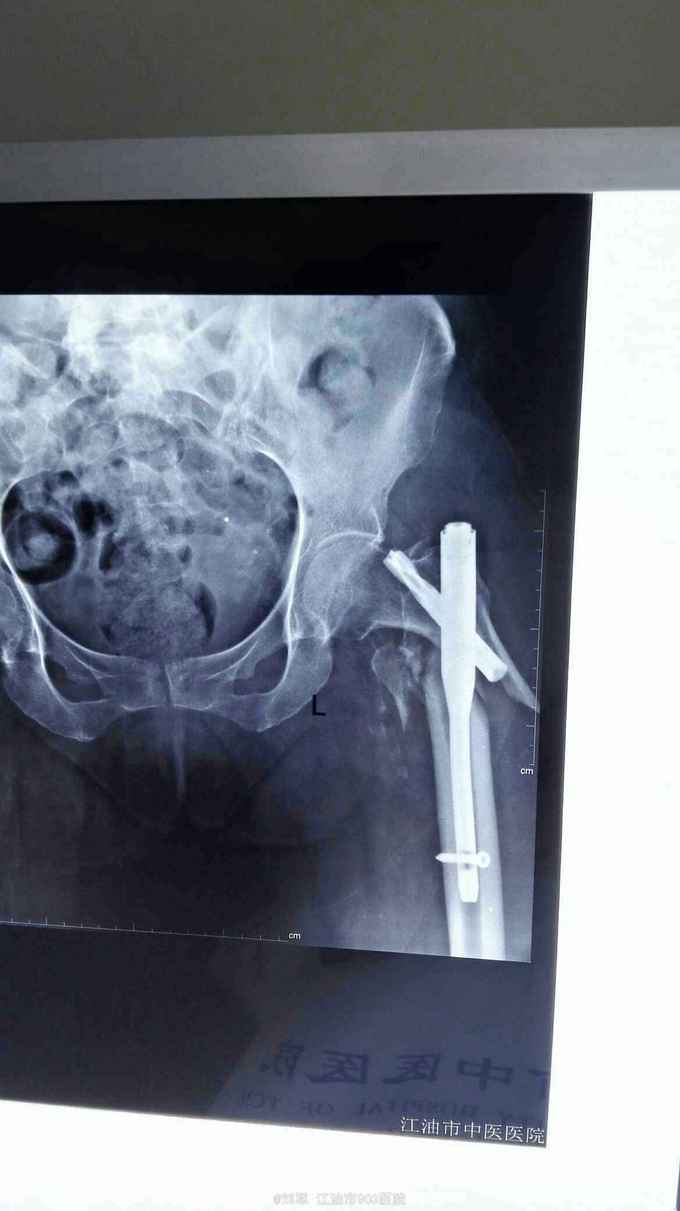

左侧股骨粗隆骨折术后骨折再移位20天。 患者74岁女性,20天前于外院行左股骨粗隆骨折PFNA内固定术。术后复查X片提示骨折再移位,内固定失败。来我院就诊。既往有糖尿病病史。入院时血糖控制可。贫血,低蛋白明显。HGB:68g/L。

左髋部肿胀,切口干燥,未拆线,无明显红肿、渗液。左髋关节活动障碍。

左股骨粗隆骨折术后再移位,2型糖尿病,